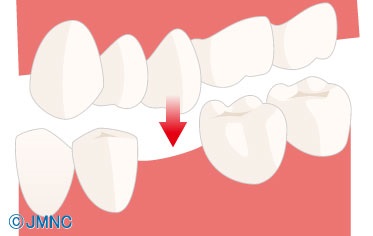

Mi történik a fogak, ha hosszú ideig nem visszaállítani törölt fogakat? Mozognak. És közben minden két szomszédos fogak elvesztek, és azokét, akik a szemközti állkapocs.

Ez a folyamat zajlik különböző mértékben különböző emberek, de az eredmény mindig ugyanaz - a képtelenség, hogy megfelelően visszaállítani a hiányzó fog, mert mert egyszerűen nincs hely maradt.

Minél több idő telik a foghúzás után megbukott protézis, annál nagyobb az eltolódás fogak. Sajnos keletkezik ebben fogazat deformációk vezethet új problémákat. A komplexitás a protézis a betegségek az állkapocsízület a jelentős malocclusions.

Például, az egyik változat szerint a törzs.